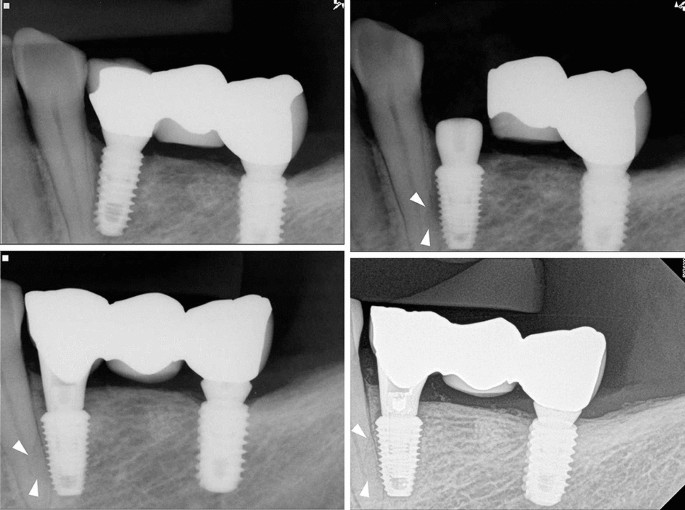

The periapical views of groups I, II and III are shown in Figs. 2, 3, 4. Of the 32 teeth, ten were in group I, ten in group II, and 12 in group III (Table 3). In group I, two out of five new endodontically treated teeth were extracted with symptoms. Consequently, five of 10 teeth in group I had events. The remaining five teeth consisted of two endodontically treated teeth prior to implant surgery and three vital teeth with non-specific findings. Fig. 2 shows the healing aspect of one of three vital teeth in group I and a replaced implant with a new one due to failure in osseointegration, which was the only case of implant failure in the study. In group II, one of the vital teeth had symptoms and underwent RCT. In group III, a new RCT was performed on one vital tooth, which was subsequently extracted. There were no implant failures in groups II and III. Events among the three groups showed significant differences (Chi-square test, p=0.008).

The patients complained only of a few clinical symptoms, even when the implant injured the adjacent natural teeth. Four patients complained of symptoms, and three of them were belonging to group I (directly invasion by the implant). Immediately after surgery, one patient with the implant in the maxillary right first premolar area complained of tenderness on percussion of the maxillary right canine, which had already been endodontically treated. However, the symptom disappeared after several days. Another patient in group II complained of tooth discomfort after surgery and underwent RCT with signs of pulp necrosis. Yet another patient complained of minute tooth discomfort after surgery, and intentional replantation was performed five years later. The last patient reported intermittent inconvenience during mastication with the tooth which had undergone RCT one month after loading. Eventually, the tooth was extracted three years and three months later with discomfort.

In the result of present study, there was a significant difference in complication rates between the groups. When compared with groups II or III, group I showed relatively higher cases of pulp devitalization (five of 10 teeth) and progressive mobility for some years after damage. When invasion was limited to the periodontal ligament or was close to the root surface, the incidence of events was lower, but direct invasion of the root resulted in a higher rate of loss of vitality and/or subsequent extraction. Previous studies have shown that healing does not occur to the same extent in all cases. The pattern of repair differs according to the magnitude and nature of damage17,18,20,21,22. Minimally damaged roots did not adversely affect the healing process18. Conversely, if the pulp was invaded by the miniscrew, little or no healing occurred17,21.